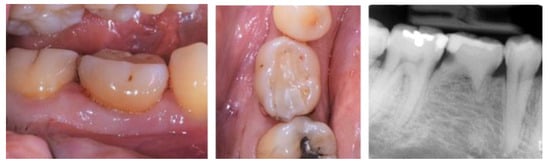

- Case 1:

- Case 2:

- Case 3:

- Case 4:

- Case 5: